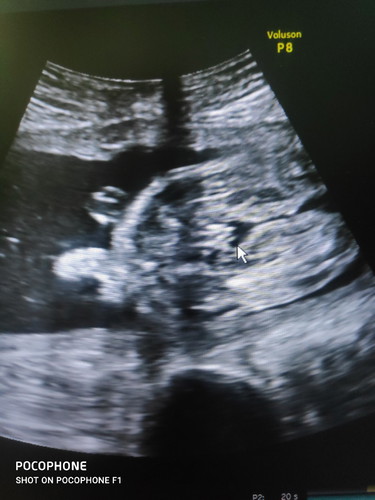

คุณแม่ ว่า ผู้หญิง หรือ ผู้ชายคะ

หมอบอกแนวโน้มไปทางผู้หญิง

ดูยากมากค่ะเเม่ อาจจะผู้หญิง เเต่คิดว่าผู้หญิงมากกว่าค่ะ ถ้าเพศชาย จะเห็นได้ชัดกว่าเพศหญิง หมอฟันธงกี่%คะ